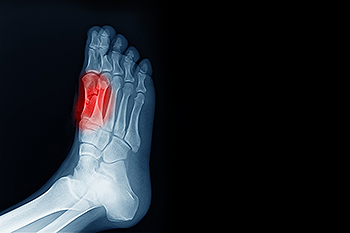

Sesamoiditis affects the small sesamoid bones located beneath the big toe joint. These bones help support movement and absorb pressure when walking and running. Sesamoiditis is considered a cause of pain and inflammation in the ball of the foot. Signs of this condition may include tenderness under the big toe joint, swelling, difficulty bending the toe, and discomfort during weight-bearing activity. Causes often involve repetitive stress, high-impact sports, or footwear that increases pressure on the forefoot. Risk factors include running, dancing, and wearing high-heeled shoes. A podiatrist can diagnose the condition and provide targeted treatment. If you have pain in this part of your foot, it is suggested that you consult a podiatrist who can diagnose the cause and provide appropriate relief and treatment solutions.

Sesamoiditis is a condition of the foot that affects the ball of the foot. It is more common in younger people than it is in older people. It can also occur with people who have begun a new exercise program, since their bodies are adjusting to the new physical regimen. Pain may also be caused by the inflammation of tendons surrounding the bones. It is important to seek treatment in its early stages because if you ignore the pain, this condition can lead to more serious problems such as severe irritation and bone fractures.